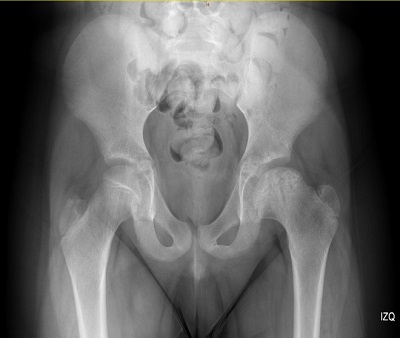

La radiografía (Figura 1) desvela una hiperlucencia de la epífisis de la cabeza femoral izquierda con reducción del grosor epifisiario y fragmentación parcial con alteración del contorno fisario, estableciendo apariencia de coxa magna y plana. Hallazgos compatibles con enfermedad de Legg-Calvé-Perthes estadio II de Waldeström, Herring a-b.

| Figura 1. Hiperlucencia de la epífisis de la cabeza femoral izquierda con reducción del grosor epifisiario y fragmentación parcial |